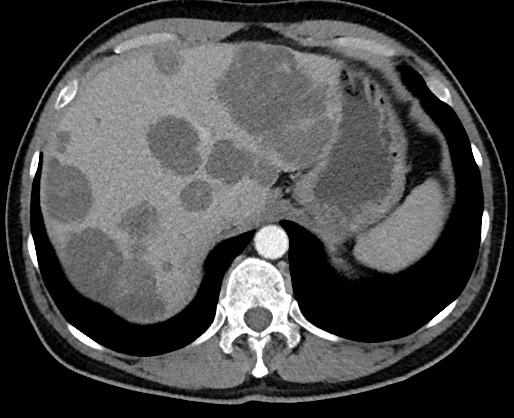

Your patient is 4 years s/p LAR and surveillance CT reveals the following. Estimated functional reserve is 20%. This is his surgical option.

Liver Transplant